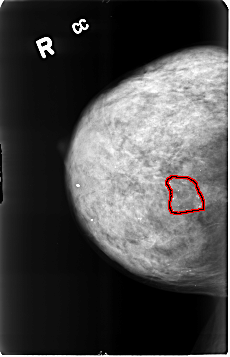

B_3210_1.RIGHT_CC

FILE: B_3210_1.RIGHT_CC.OVERLAY

TOTAL_ABNORMALITIES 1

ABNORMALITY 1

LESION_TYPE CALCIFICATION TYPE VASCULAR-COARSE-LUCENT_CENTER-ROUND_AND_REGULAR-PUNCTATE DISTRIBUTION REGIONAL

ASSESSMENT 2

SUBTLETY 5

PATHOLOGY BENIGN_WITHOUT_CALLBACK

TOTAL_OUTLINES 1

BOUNDARY